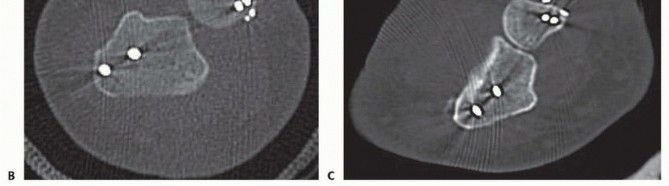

Anteroposterior and lateral radiographs of the wrist, forearm, and elbow suffice for diagnosing Galeazzi fracturedislocations. At presentation, radiographs typically demonstrate the following: Shortening of the radius on the anteroposterior view with a widened DRUJ Apex medial angulation of the distal radial segment (toward the ulna) An apex dorsal angulation of the radius on the lateral radiograph with a dorsal dislocation of the DRUJ An ulnar styloid base fracture may also be present. DRUJ subluxation is notoriously difficult to identify. Postoperatively, if there is any concern whether the DRUJ is reduced, computed tomography (CT) or magnetic resonance imaging (MRI) should be obtained. The DRUJ is well visualized in the axial plane to determine subluxation or dislocation. Multiple methods have been devised to identify and quantify DRUJ subluxation using CT (Mino's criteria, congruency method, epicenter method, and radioulnar ratio).11 Unfortunately, no reference standard exists (

### FIG 3A-C).

### FIG 3 • A. Radioulnar ratio method to measure DRUJ subluxation on a CT scan. See text for details. B. Axial CT scan demonstrating dorsally dislocated ulna following ulnar styloid open reduction internal fixation (ORIF). C. Axial CT scan following reduction and pinning of the dislocated DRUJ. (A: Adapted from Lo IK, MacDermid JC, Bennett JD, et al. The radioulnar ratio: a new method of quantifying DRUJ subluxation. J Hand Surg Am 2001;26:236-243.)